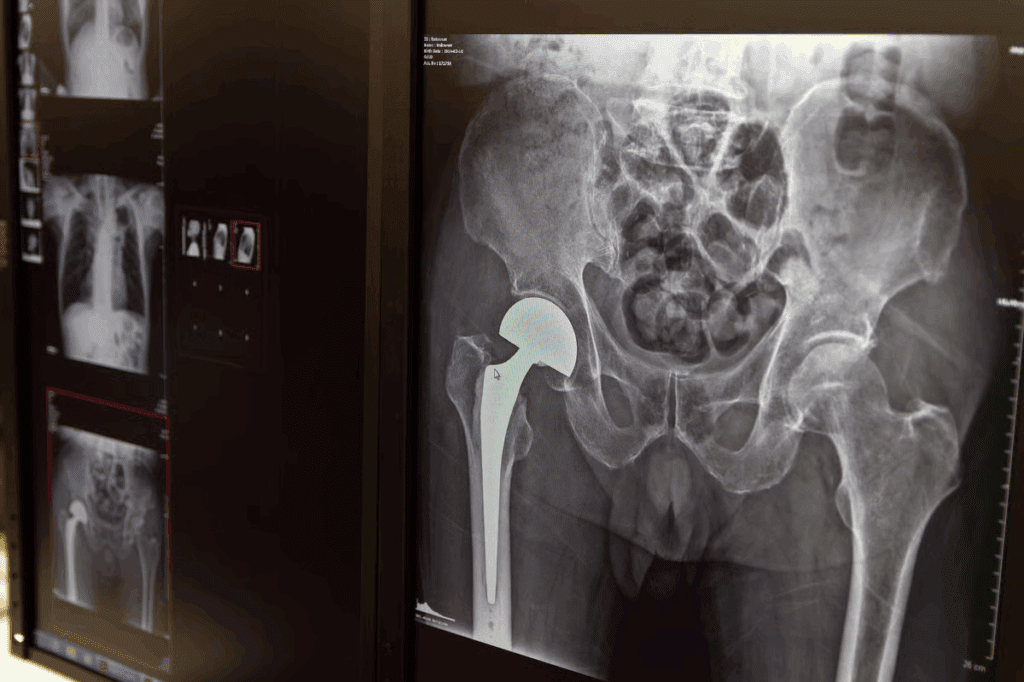

Hip Fractures: Life-Changing Injuries

Hip fractures are very serious injuries. They affect not just how you move but also your overall health. The recovery is long and hard, changing your life a lot.

Types of Hip Fractures and Their Severity

Hip fractures are divided into types based on where and how bad they are. The most common are intracapsular and extracapsular fractures. Knowing the type and severity helps doctors choose the right treatment and predict how well you’ll do.

Doctors use the Garden classification for intracapsular fractures and the AO/OTA classification for extracapsular ones. These systems help doctors understand how complex the fracture is and decide on treatment.

Hip Fracture Recovery Timeline and Mobility Challenges

The time it takes to recover from a hip fracture varies. It depends on your health, how bad the fracture is, and the treatment. Usually, it takes several months. Moving around early is important to avoid problems like blood clots and pneumonia.

Mortality Rates and Long-term Independence Concerns

Hip fractures are linked to high death rates, mainly in older people. The death rate in the first year after a hip fracture can be up to 30%. Many worry about keeping their independence long-term, as they may need ongoing care.

Things that affect how long you live and your independence include your age, other health issues, and how well you could move before the fracture. Knowing these helps doctors give better care and improve your chances of a good outcome.